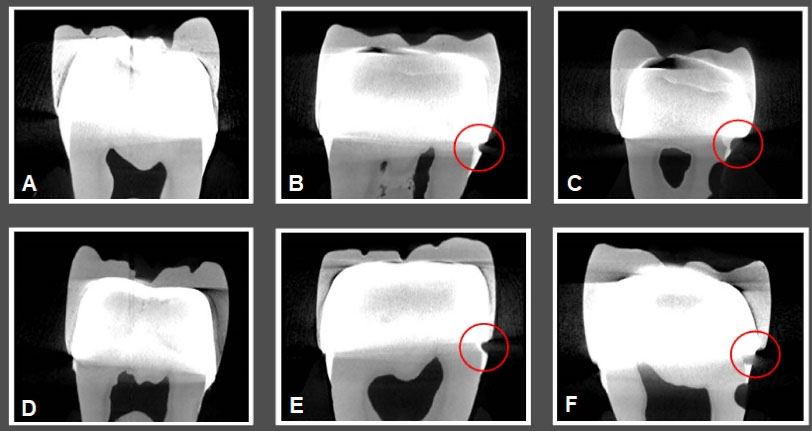

and illustrate CBCT and micro-CT images obtained from teeth restored with metal-ceramic and all-ceramic crowns.

Figure 4.

CBCT Images. A. All-ceramic crown without a gap. B. All-ceramic crown with a gap of 0.3 mm. C. All-ceramic crown with a gap of 0.5 mm. D. Metal-ceramic crown without a gap. E. Metal-ceramic crown with a gap of 0.3 mm. F. Metal-ceramic crown with a gap of 0.5 mm